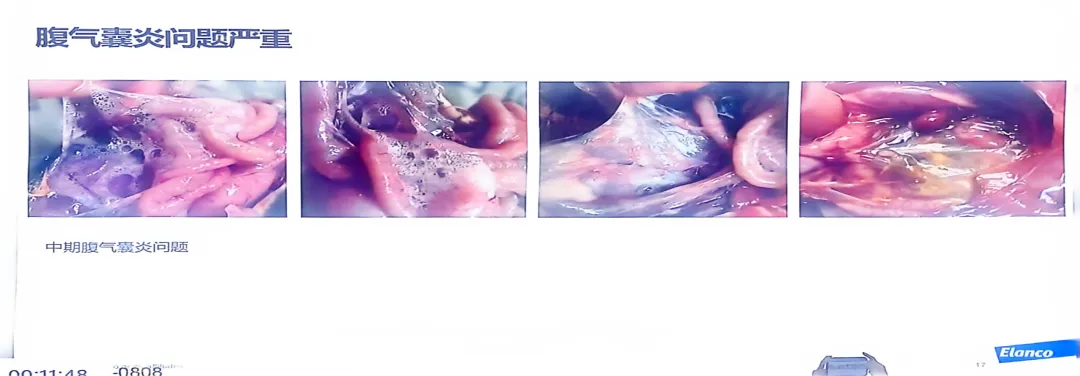

>精品课件!!鸡支原体的危害及防控思路

精品课件!!鸡支原体的危害及防控思路